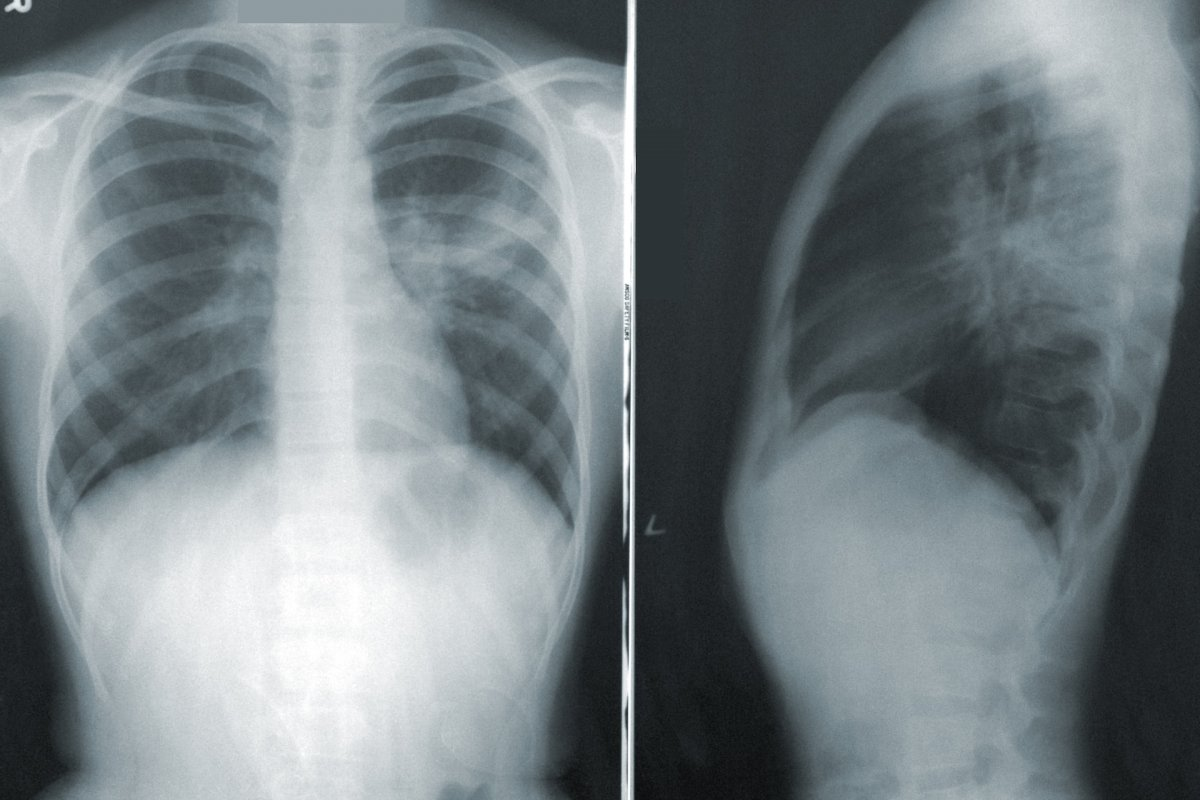

Laboratory Tests and Imaging

Lab tests are key to confirming viral pneumonia. Complete Blood Count (CBC) shows if there’s an infection. Viral PCR (Polymerase Chain Reaction) tests can find the virus. Chest X-rays or CT scans show how much of the lung is affected.

- Chest X-rays or CT scans to evaluate lung involvement

Telling viral from bacterial pneumonia is important. We use symptoms, lab results, and images together. Certain chest images are more common in viral cases.